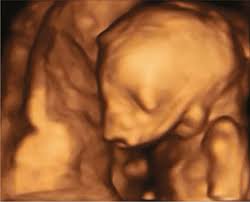

12 Weeks 1 Day Ultrasound Video Dailymotion

12 Weeks 1 Day Ultrasound Video Dailymotion from s1.dmcdn.net